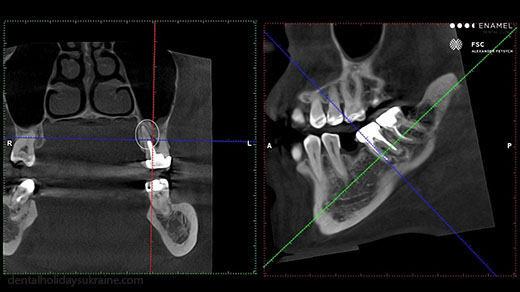

In planning involved several doctors: Endodontists, implant and orthodontist. Planning may require additional examinations: orthopantomogram, dental photography, computer tomography, functional diagnostics, digital smile design After analyzing all the information, there is a presentation of the plan treatment with an explanation of the required interventions, methods, steps, alternatives and cost estimates.